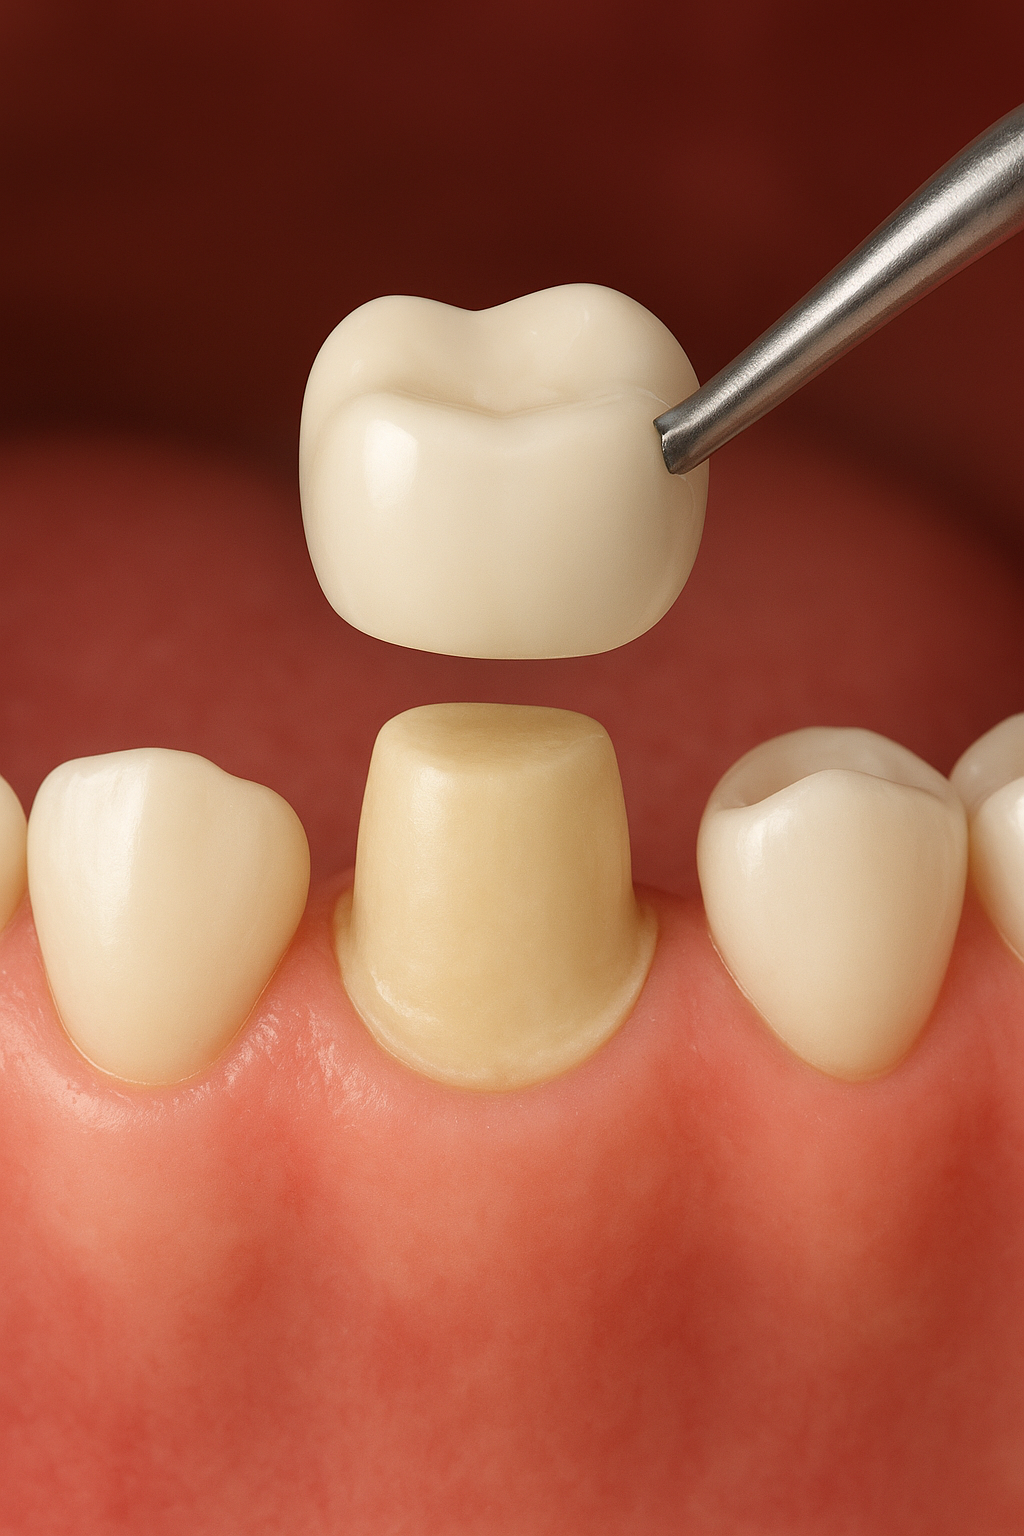

Diagram showing how a dental crown fits over a natural tooth

A dental crown, also known as a “cap,” is a protective cover placed on a tooth to reinforce and strengthen it.

A dental crown is a protective cap that gets fitted over a damaged tooth to strengthen, restore its strength and make it healthy again. For folks in Winchester, crowns are often used to save teeth that have been compromised by tooth decay, cracks, breaks or huge fillings.

To accommodate the crown, the dentist carefully reshapes or shaves down the tooth. After reshaping, the dentist takes an impression of the tooth to ensure the crown fits precisely.